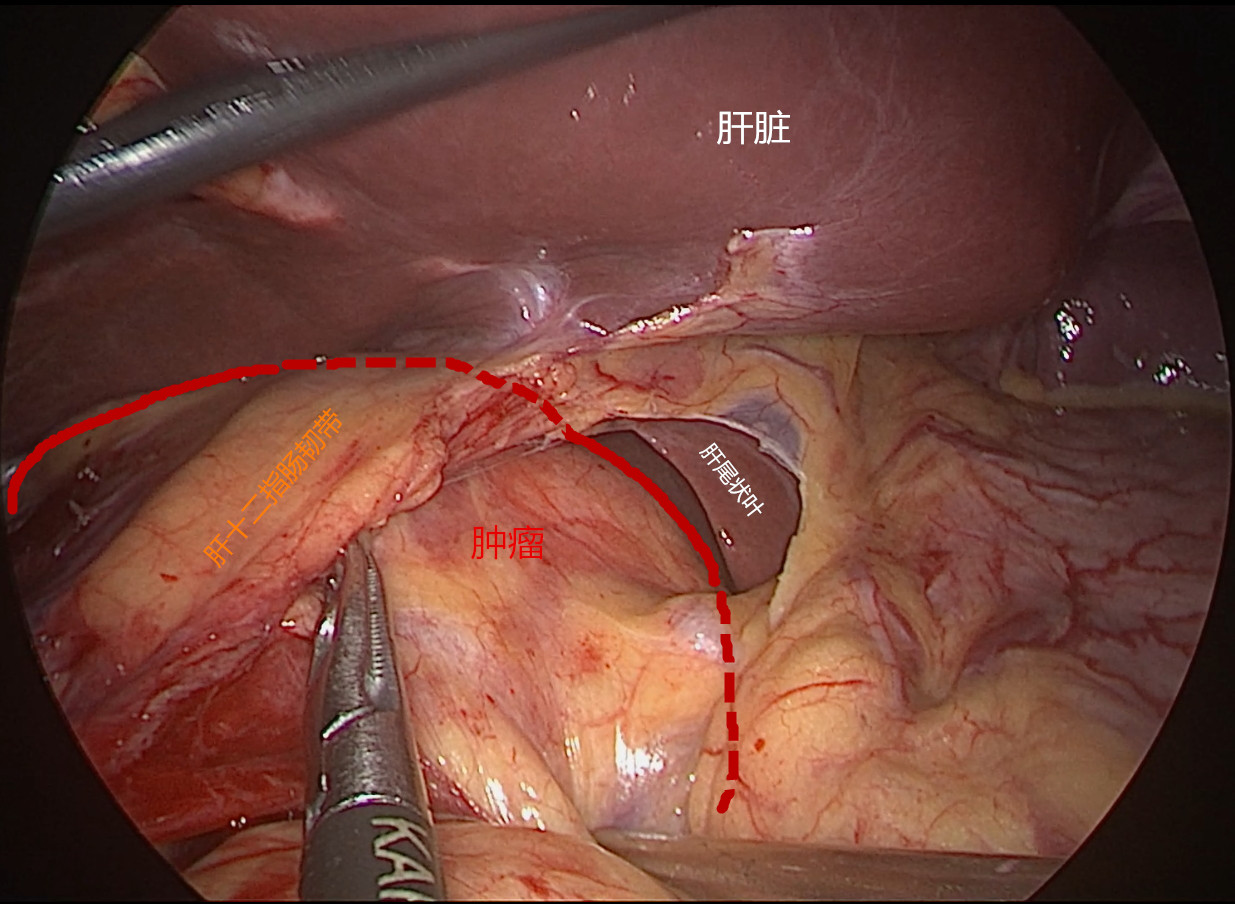

患者女性,45岁,体检发现后腹膜占位2月。CT提示:“胰腺后方可见约63*90mm混杂密度肿块影,内可见囊实性区及脂肪、牙齿,增强扫描实性区动脉期轻度强化,门脉期明显强化,边界清;腹腔干、肠系膜上动脉受压移位,考虑畸胎瘤诊断”。患者后腹膜占位诊断明确,肿瘤较大周围脏器受压,手术指征明确,拟行腹腔镜手术探查。手术困难所在:1.病变位于肝十二指肠韧带、十二指肠、胰头及横结肠后方暴露困难;2.毗邻关系复杂,病变周围与肝脏、胆囊、胆总管、横结肠、胃窦、十二指肠及胰头等重要器官毗邻;3.周围大血管多,病变与门静脉、肝总动脉、腹腔干、肠系膜动静脉、下腔静脉及左肾静脉关系密切,易导致术中大出血;4.病变系囊实性肿块牵引提拉困难。今经过团队两个小时的努力顺利切除肿瘤,术中出血约100ml。感谢麻醉师、护士及团队的辛勤付出,祝患者早日康复。